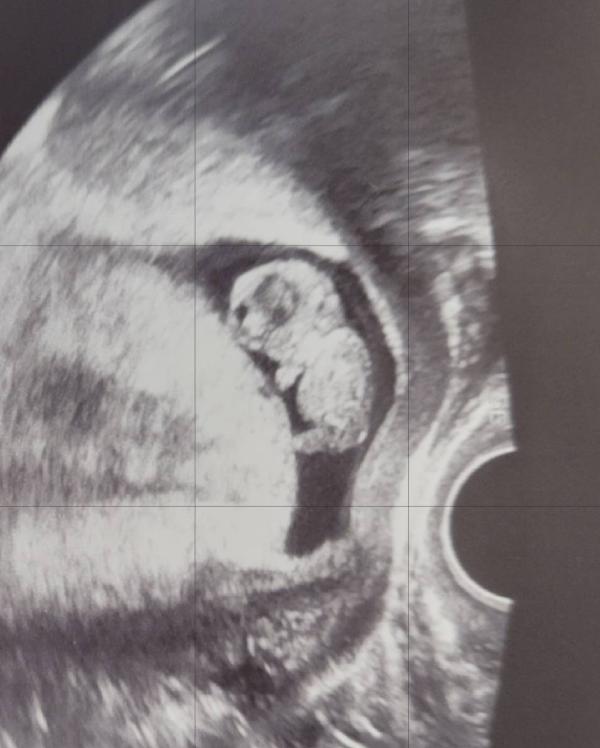

Ну а мы потихоньку растем, скоро уже 1й скрининг. Верю в то, что все хорошо , но нотки волнения конечно же есть. Интересно, можно ли взять мужа с собой:/ В женской консультации в Спб к этому спокойно относятся, как это в Челябинске не знаю🫣

У меня был 1скрининг в жк 🤦🏼♀️. С мужем нельзя , они даже не дали посмотреть на монитор, ни распечатали , толком ниче не говорили. На 2скрининг опять записали в жк , я отказалась. Пойдём вместе с мужем платно сделаем, и покажут и расскажут нам и распечатают фоточки.

Я ходила на все УЗИ платно и мужа пускали на все УЗИ, если УЗИ было по животу.

Если платно делаете, то они сами предлагают вдвоем зайти